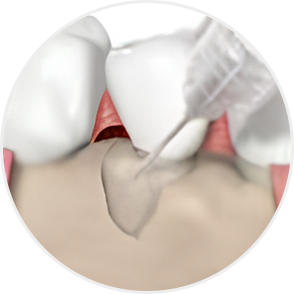

STEP 04

Emdogain application

-

STEP 05

Cleansing

STEP 06

Flap closure and suturing